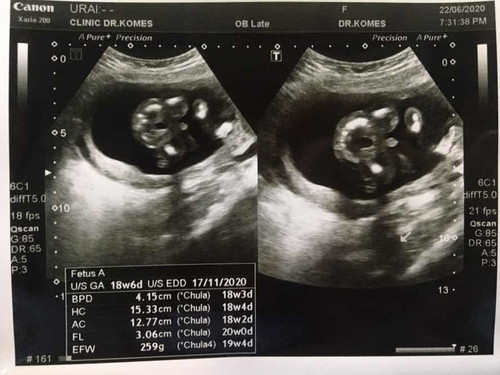

แม่ๆอวดรูปซาวกันหน่อยค่ะว่าได้ผู้ชายหรือผู้หญิง

หมอนัดไปซาวเห็นอิจู๋ผมไหมคับ ผมมีอิจู๋น้ะสมใจพ่อเลยบ้านนี้ 👶🏻🥰

ชายจ้า